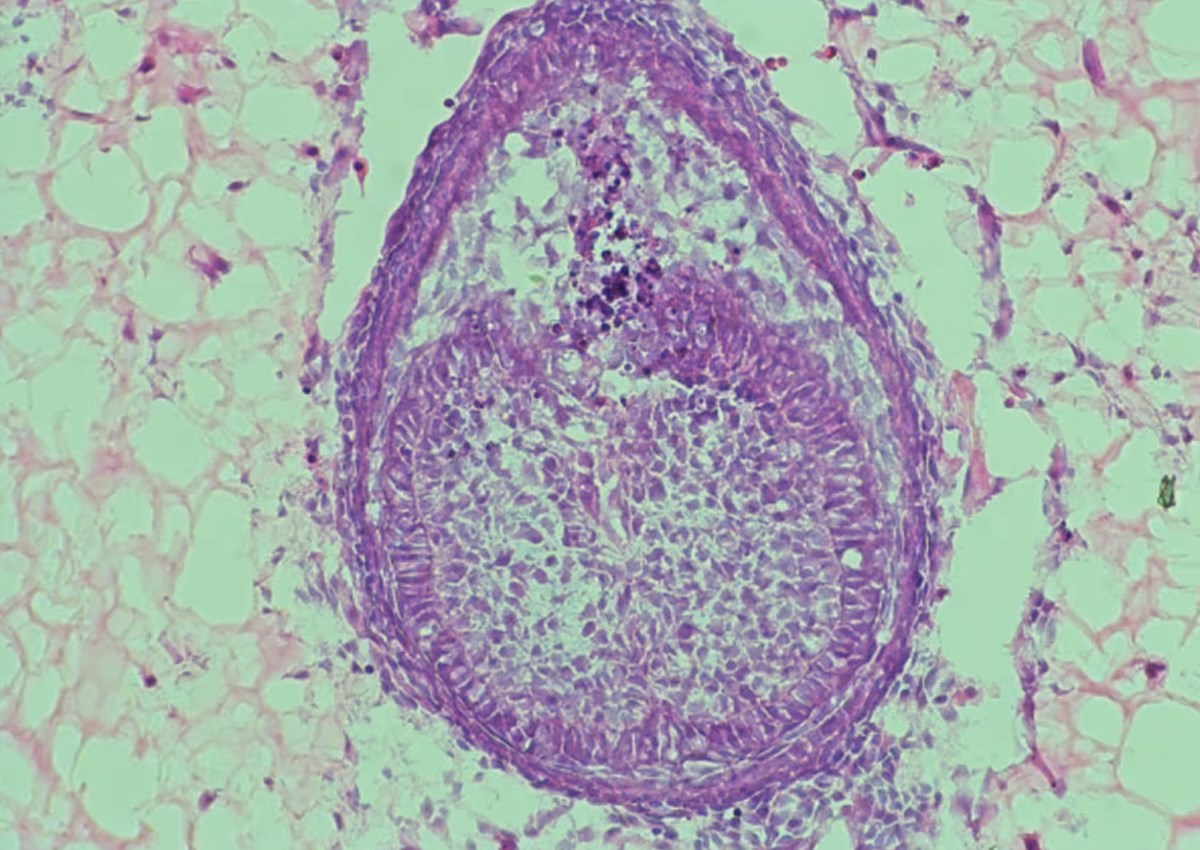

To okruženje, koje znanstvenici nazivaju "skelom", ključno je za uspjeh. U najnovijoj studiji, umjesto kolagena korištenog 2013., tim sada koristi hidrogel, polimer s visokim udjelom vode. "Prvo prikupljamo stanice iz mišjih embrija, zatim ih miješamo i centrifugiramo kako bismo dobili malu staničnu kuglicu. Zatim ubrizgavamo tu kuglicu u hidrogel i uzgajamo je oko osam dana", objasnio je Xuechen Zhang, doktorand na King's Collegeu i koautor studije. Nakon osam dana, unutar hidrogela formiraju se strukture nalik zubima. U prethodnom istraživanju, takvi "zubni zameci" preneseni su u miša gdje su se razvili u zubnu strukturu s korijenom i caklinom.